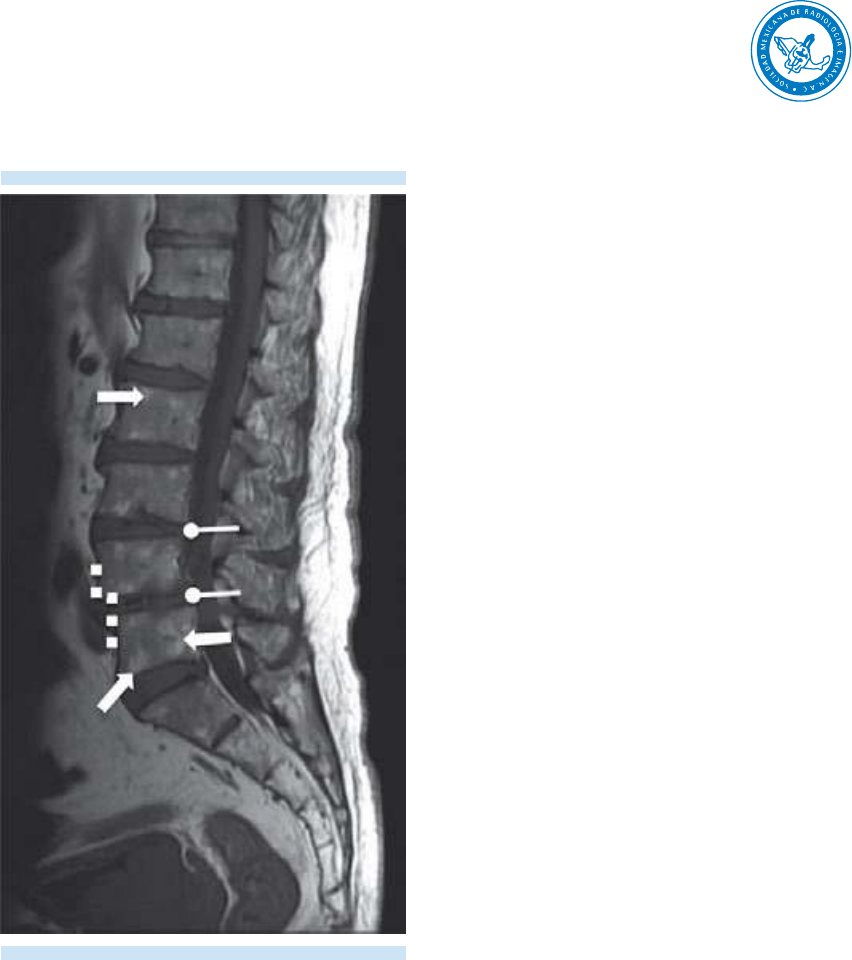

La resonancia magnética es el método de imagen

de elección para el estudio de la columna verte-

bral y una herramienta valiosa en la detección

de anormalidades óseas y de la médula espinal.

Un adecuado conocimiento de la anatomía de

la columna lumbar y de cada uno de sus com-

ponentes, así como la elaboración de un reporte

idóneo por parte del especialista en imagen,

aportará al clínico los elementos necesarios para

el adecuado manejo del paciente.